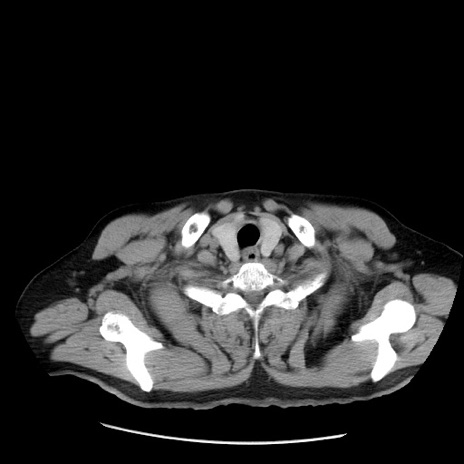

冠状断像

矢状断像